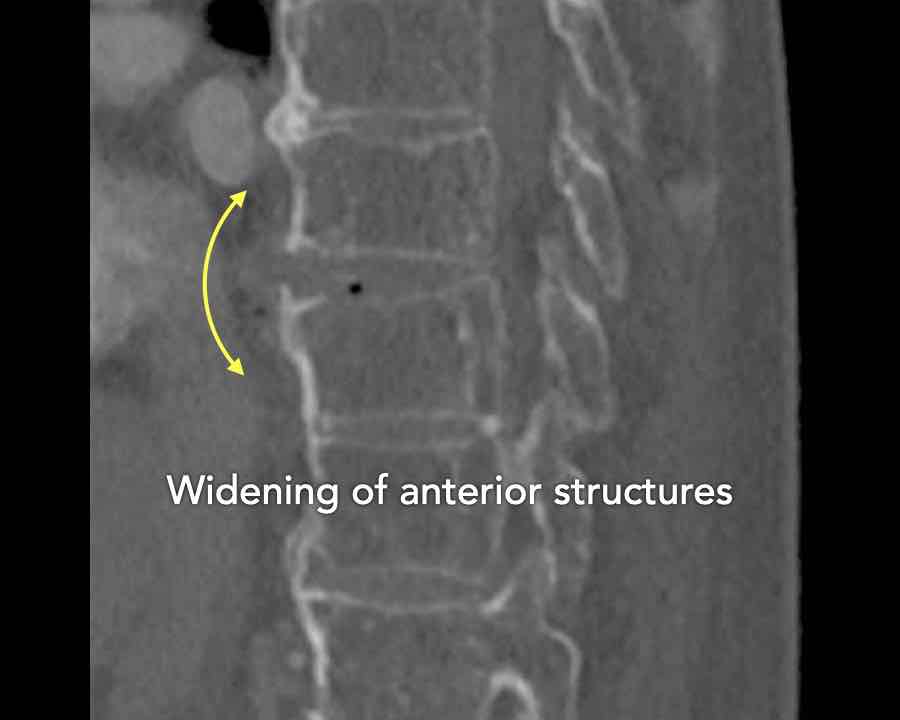

B3 Extension distraction injury

Hyperextension can result in distraction of the anterior tension band, which is formed by the vertebral bodies, the anterior and posterior longitudinal ligaments and the intervertebral disc.

These injuries can be difficult to detect since patients are scanned in the supine position laying on their back, which may obscure the anterior distraction.

Extension distraction is characterized by:

- Distraction of the tension band on the anterior side.

- Any horizontal or oblique fracture line through vertebral bodies anteriorly with separation on both sides.

- Widening of intervertebral disc space.

Scroll through images.

What are the findings?

Findings

- C injury? No.

- Signs of a rigid spine?

Yes, a B3 injury is very likely. - A subtle fracture on the anterior vertebral body.

Conclusion

Injury type B3.